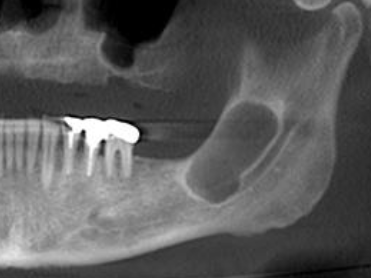

how would you describe this radiographic lesion?

a multilocular radiolucent lesion